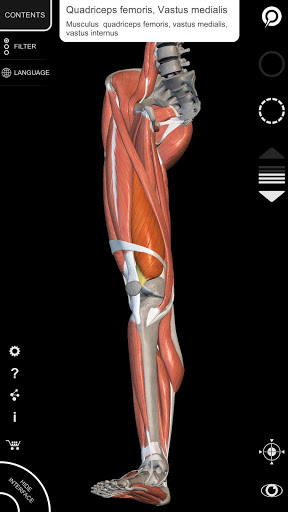

"Anatomy 3D Atlas" vous permet d'étudier l'anatomie humaine de manière simple et interactive.

Grâce à une interface simple et intuitive, il est possible d'observer chaque structure anatomique sous n'importe quel angle.

Les modèles anatomiques 3D sont particulièrement détaillés et avec des textures jusqu'à une résolution de 4k.

• Système musculo-squelettique

• Faites pivoter et zoomez chaque modèle dans l'espace 3D

• Visualisation des muscles à travers des niveaux de couches depuis les plus superficielles jusqu'aux plus profondes

• En sélectionnant un modèle ou une épingle, le terme anatomique associé apparaît

• Description des muscles : origine, insertion, innervation et action